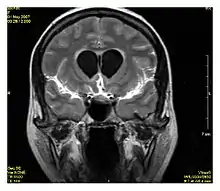

| Fluid-attenuated inversion recovery | FLAIR | Fluid suppression by setting an inversion time that nulls fluids | High signal in lacunar infarction, multiple sclerosis (MS) plaques, subarachnoid haemorrhage and meningitis (pictured).[15] |  | |